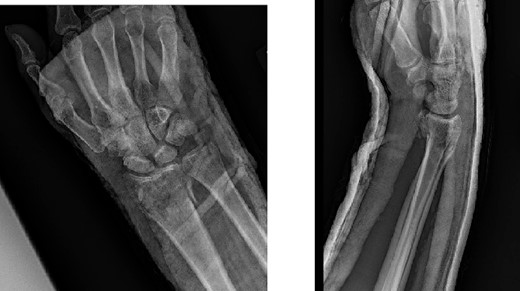

A 43-year-old man presented to the emergency department after falling ~5 ft from a ladder onto his outstretched right hand. He reported immediate pain and inability to bear weight through his right wrist. On physical examination, there was right wrist swelling and limited range of motion (ROM). The skin was intact, and neurovascular exam was normal. The patient had no other injuries and no pertinent medical history. Initial radiographic imaging confirmed a comminuted intra-articular distal radius fracture with dorsal displacement along with an ulnar styloid fracture (Fig. 1). The patient was placed in a sugar-tong splint and followed-up in clinic a week later with surgical treatment planned (Fig. 2).

Preoperative radiological assessment of the patient with postero-anterior (PA) and lateral views of the right wrist.